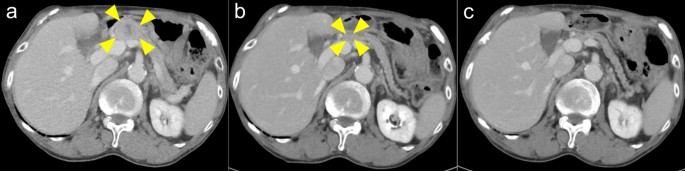

The therapeutic effects observed in 15 SDC patients were as follows: ORR, 26.7% (95%CI, 7.8–55.1); CBR, 33.3% (95%CI, 11.8–61.6); DCR, 40.0% (95%CI, 16.3–67.7); median PFS, 2.2 months (95% CI, 1.3–NE); and median OS, NR (95% CI, NE–NE) (see Supplementary Fig S1 online). None of the six patients with adenoid cystic carcinoma (AdCC) showed a response, and three of these AdCC patients died due to disease progression. Figure 2 shows images of the tumor before and during pembrolizumab monotherapy in a representative patient.

Representative images of the tumor before and during pembrolizumab monotherapy in a patient with pancreatic metastasis of salivary duct carcinoma. (a) Pre-treatment of the patient with pancreatic metastasis. (b) Tumor shrinkage observed 63 days after the initiation of pembrolizumab monotherapy. (c) Tumor disappeared 154 days after the initiation of pembrolizumab monotherapy.